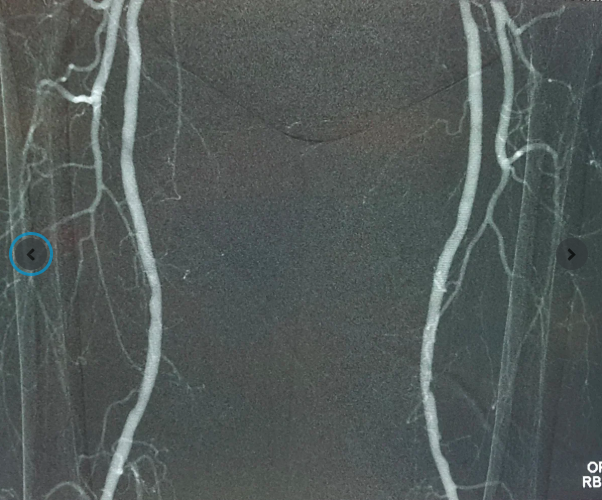

Kết quả siêu âm và chụp mạch tại FV cho thấy động mạch chậu phải bị tắc hoàn toàn đoạn dài, hẹp nặng động mạch chậu trái; động mạch chân phải bị tắc nghẽn hoàn toàn, động mạch chân trái tắc trên 90%. Máu từ tim gần như không xuống được hai chân - lý do khiến ngón chân bị hoại tử và đau nhức liên tục các ngón chân phải.

![]() |

Ca can thiệp nội mạch sử dụng khí CO2 để chụp mạch và phẫu thuật bắc cầu cho bệnh nhân N.V.Đ. |